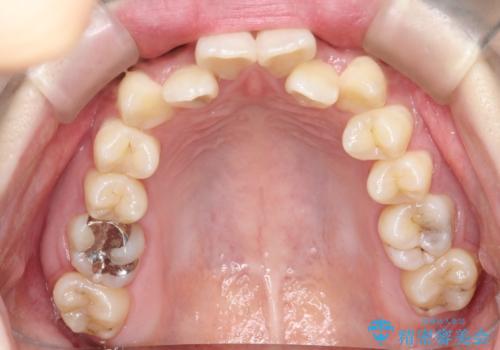

前歯が前後反対にかんでいる インビザラインによる矯正

- 前歯のがたつきを気にされて来院されました。

上顎の前から二番目の歯が内側に入り込んでおり、前後反対にかんでいる状態でした。

歯と歯の間にわずかに隙間を作り並べる計画としました。